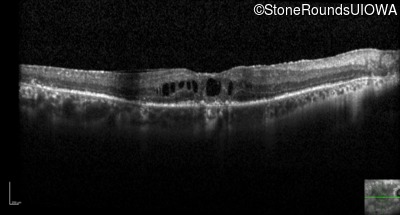

Optical Coherence Tomography - Right - 20/32

Exemplar / OCT Stack